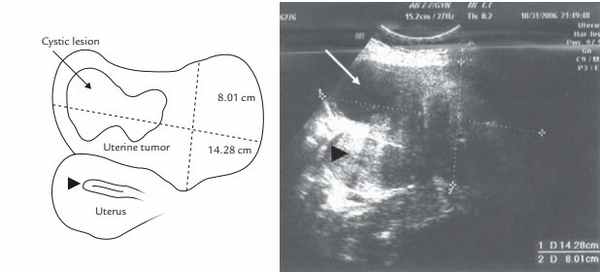

Рис. 6. УЗИ брюшной полости показывает срединный сагиттальный разрез миомы и матки (наконечник стрелки).

Обратите внимание на значительную гипоэхогенность в верхней части миомы (стрелка) по сравнению с кистозным поражением остального образца.